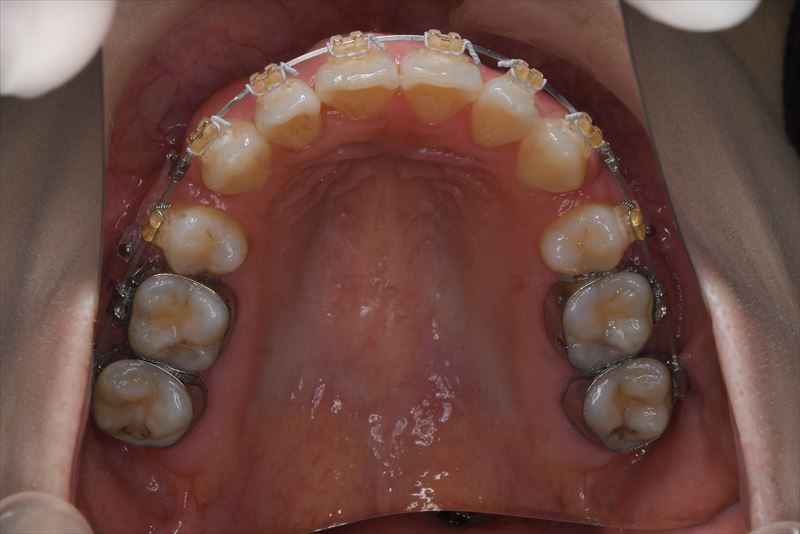

治療中

マルチブラケット装置、アンカースクリュー

上顎両側4番抜歯、下顎両側4番抜歯、下顎両側8番抜歯